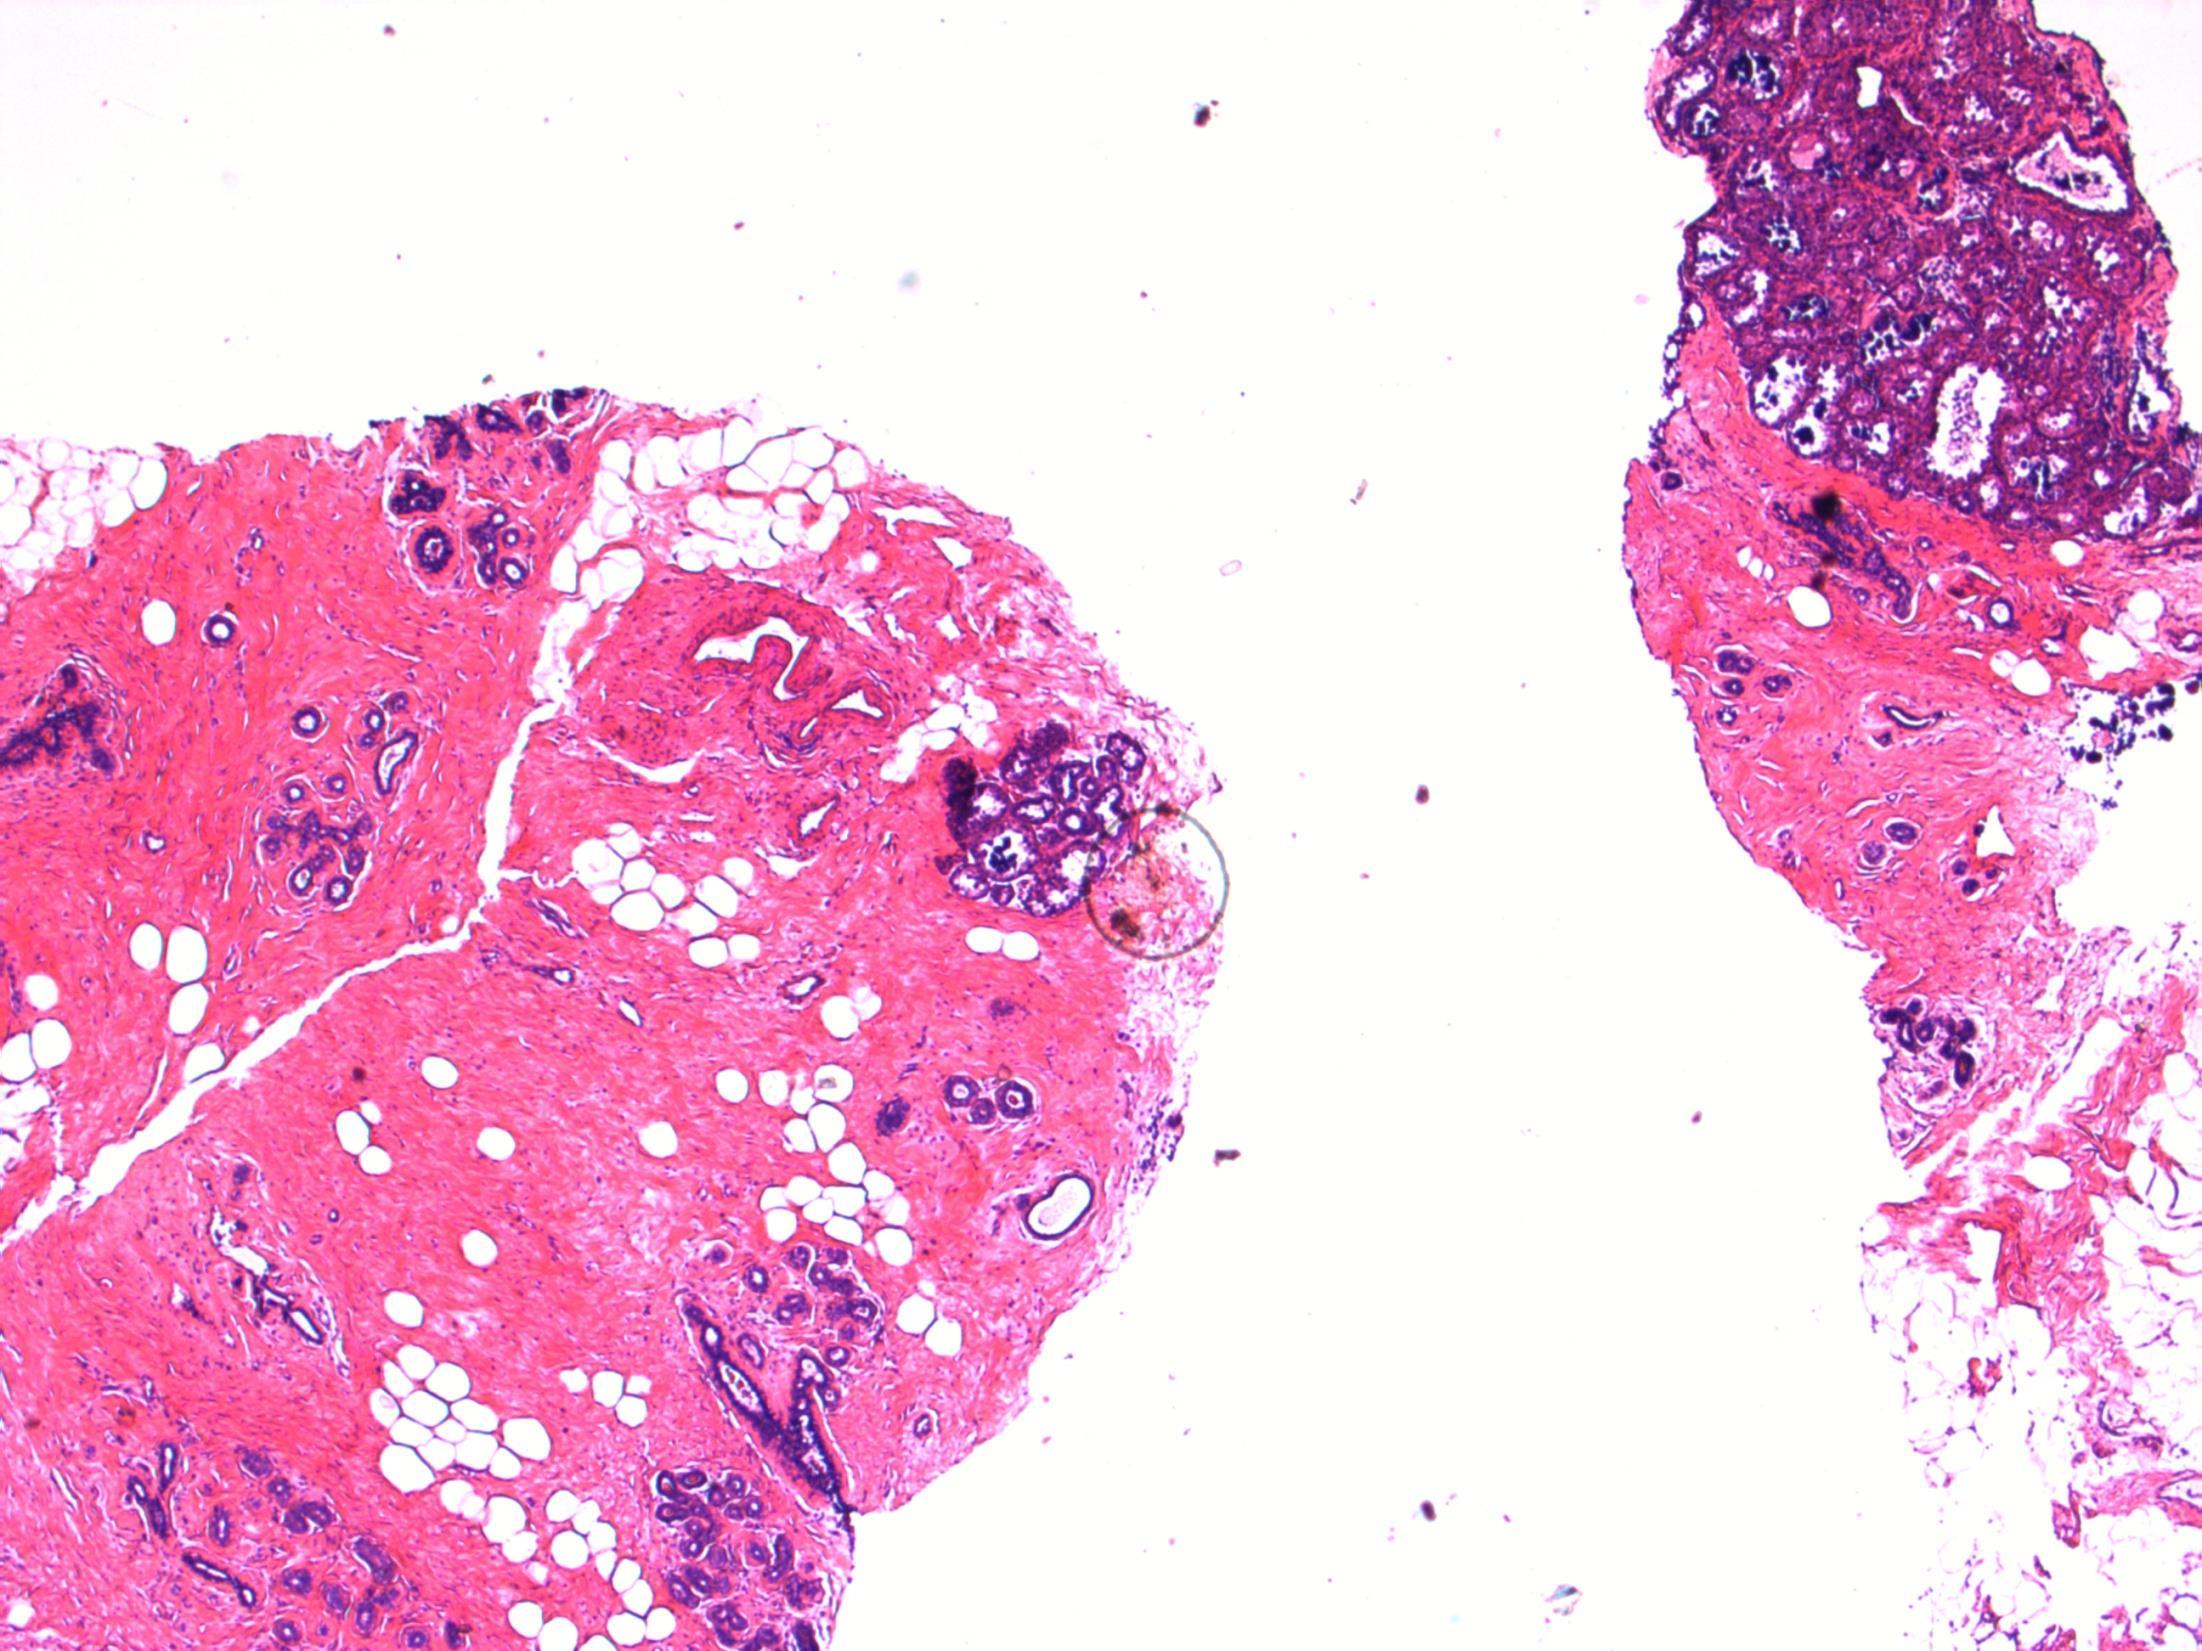

24F, Intensely itchy, excoriated papulovesicles over knees, left elbow and sacrum. Biopsy from right knee lesion. DIF from adjacent skin: Granular deposits of IgA in dermal papillae.

• Skin – Dermatitis herpetiformis

Description: Acantholytic dermatosis. Subepidermal blisters with neutrophils, oedema in papillary dermis. No evidence of malignancy.

Diagnosis: Dermatitis herpetiformis

• Linear IgA dermatosis – Children; Similar histology, DIF- IgA linear rather than granular.

• Bullous pemphigoid – Blister lumen and dermis are rich in eosinophils and neutrophils; DIF – linear deposits of IgG, C3 and IgA (40%) at DE junction.

Comments: Autoimmune– IgA against epidermal transglutanimase, association with gluten sensitive enteropathy. Does this patient have any history of coeliac disease?

Typical clinical features -excoriated, grouped papulovesicles on knee, elbow, sacrum, as described in this clinical history. DIF – Granular deposits of IgA in papillary dermis and D-E junction as described for this patient.